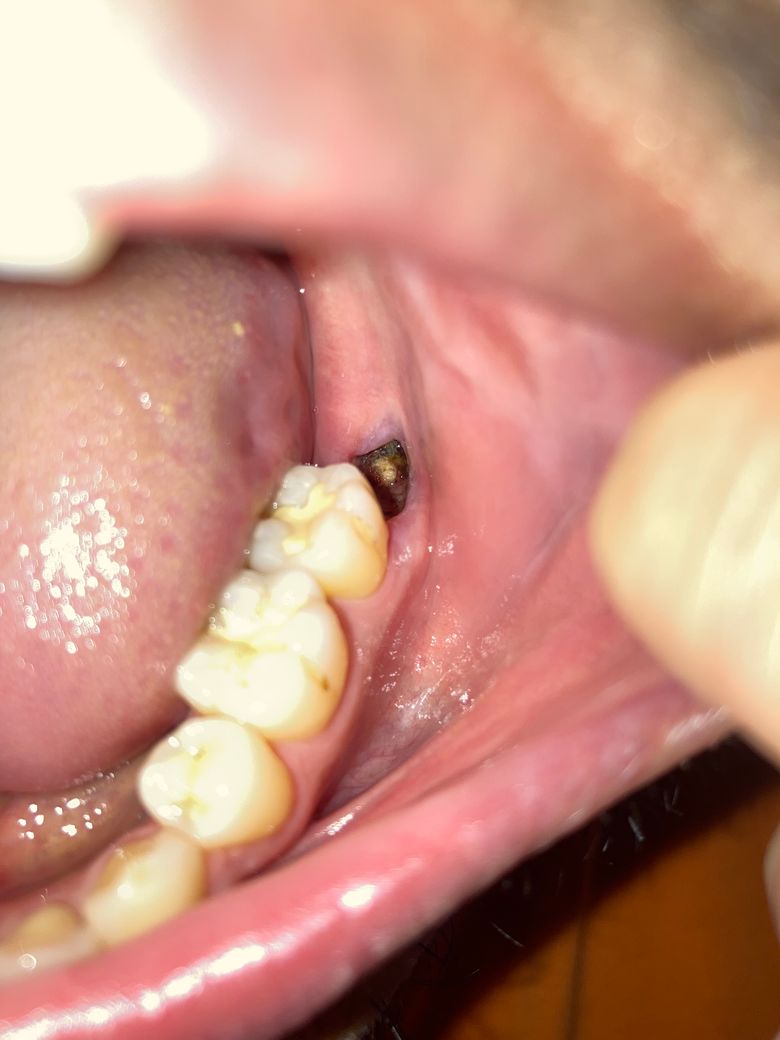

사랑니 발치 5일차 잘 회복중인 건가요?

5일 전 양쪽 사랑니 발치했습니다. 매복은 아니어서 봉합은 하지 않았습니다.

사진상으로 보았을 때 잘 아무는 중인지 판단 가능할까요?

• 1번 째 사진

사랑니를 발치한 후 해당 부위의 혈병이 완전히 형성되지 않은 것으로 보입니다 발치한 부위를 자극하지 않는 것이 좋습니다 발치를 한 부위는 자극을 하지 않는다면 일반적으로 2주 정도 지나면 아물게 됩니다.

사진상을 보면 크게 문제가 잇어 보이진 않습니다. 음식물등이 발치한공간에들어가 잇는상태이니 치과에 가셔서 소독한번 받아보시는게 좋을것같습니다.

사진상으로 발치부위가 잘 아무는 것으로 보이며, 해당부위에 염증이 덧나지 않도록 소독용 헥사메딘 가글액으로 가글하여 관리하길 권합니다.

1. 사진상으로 정확히 파악은 어려우나 별다른 증상이 없다면 큰 이상은 없는 것으로 보입니다.